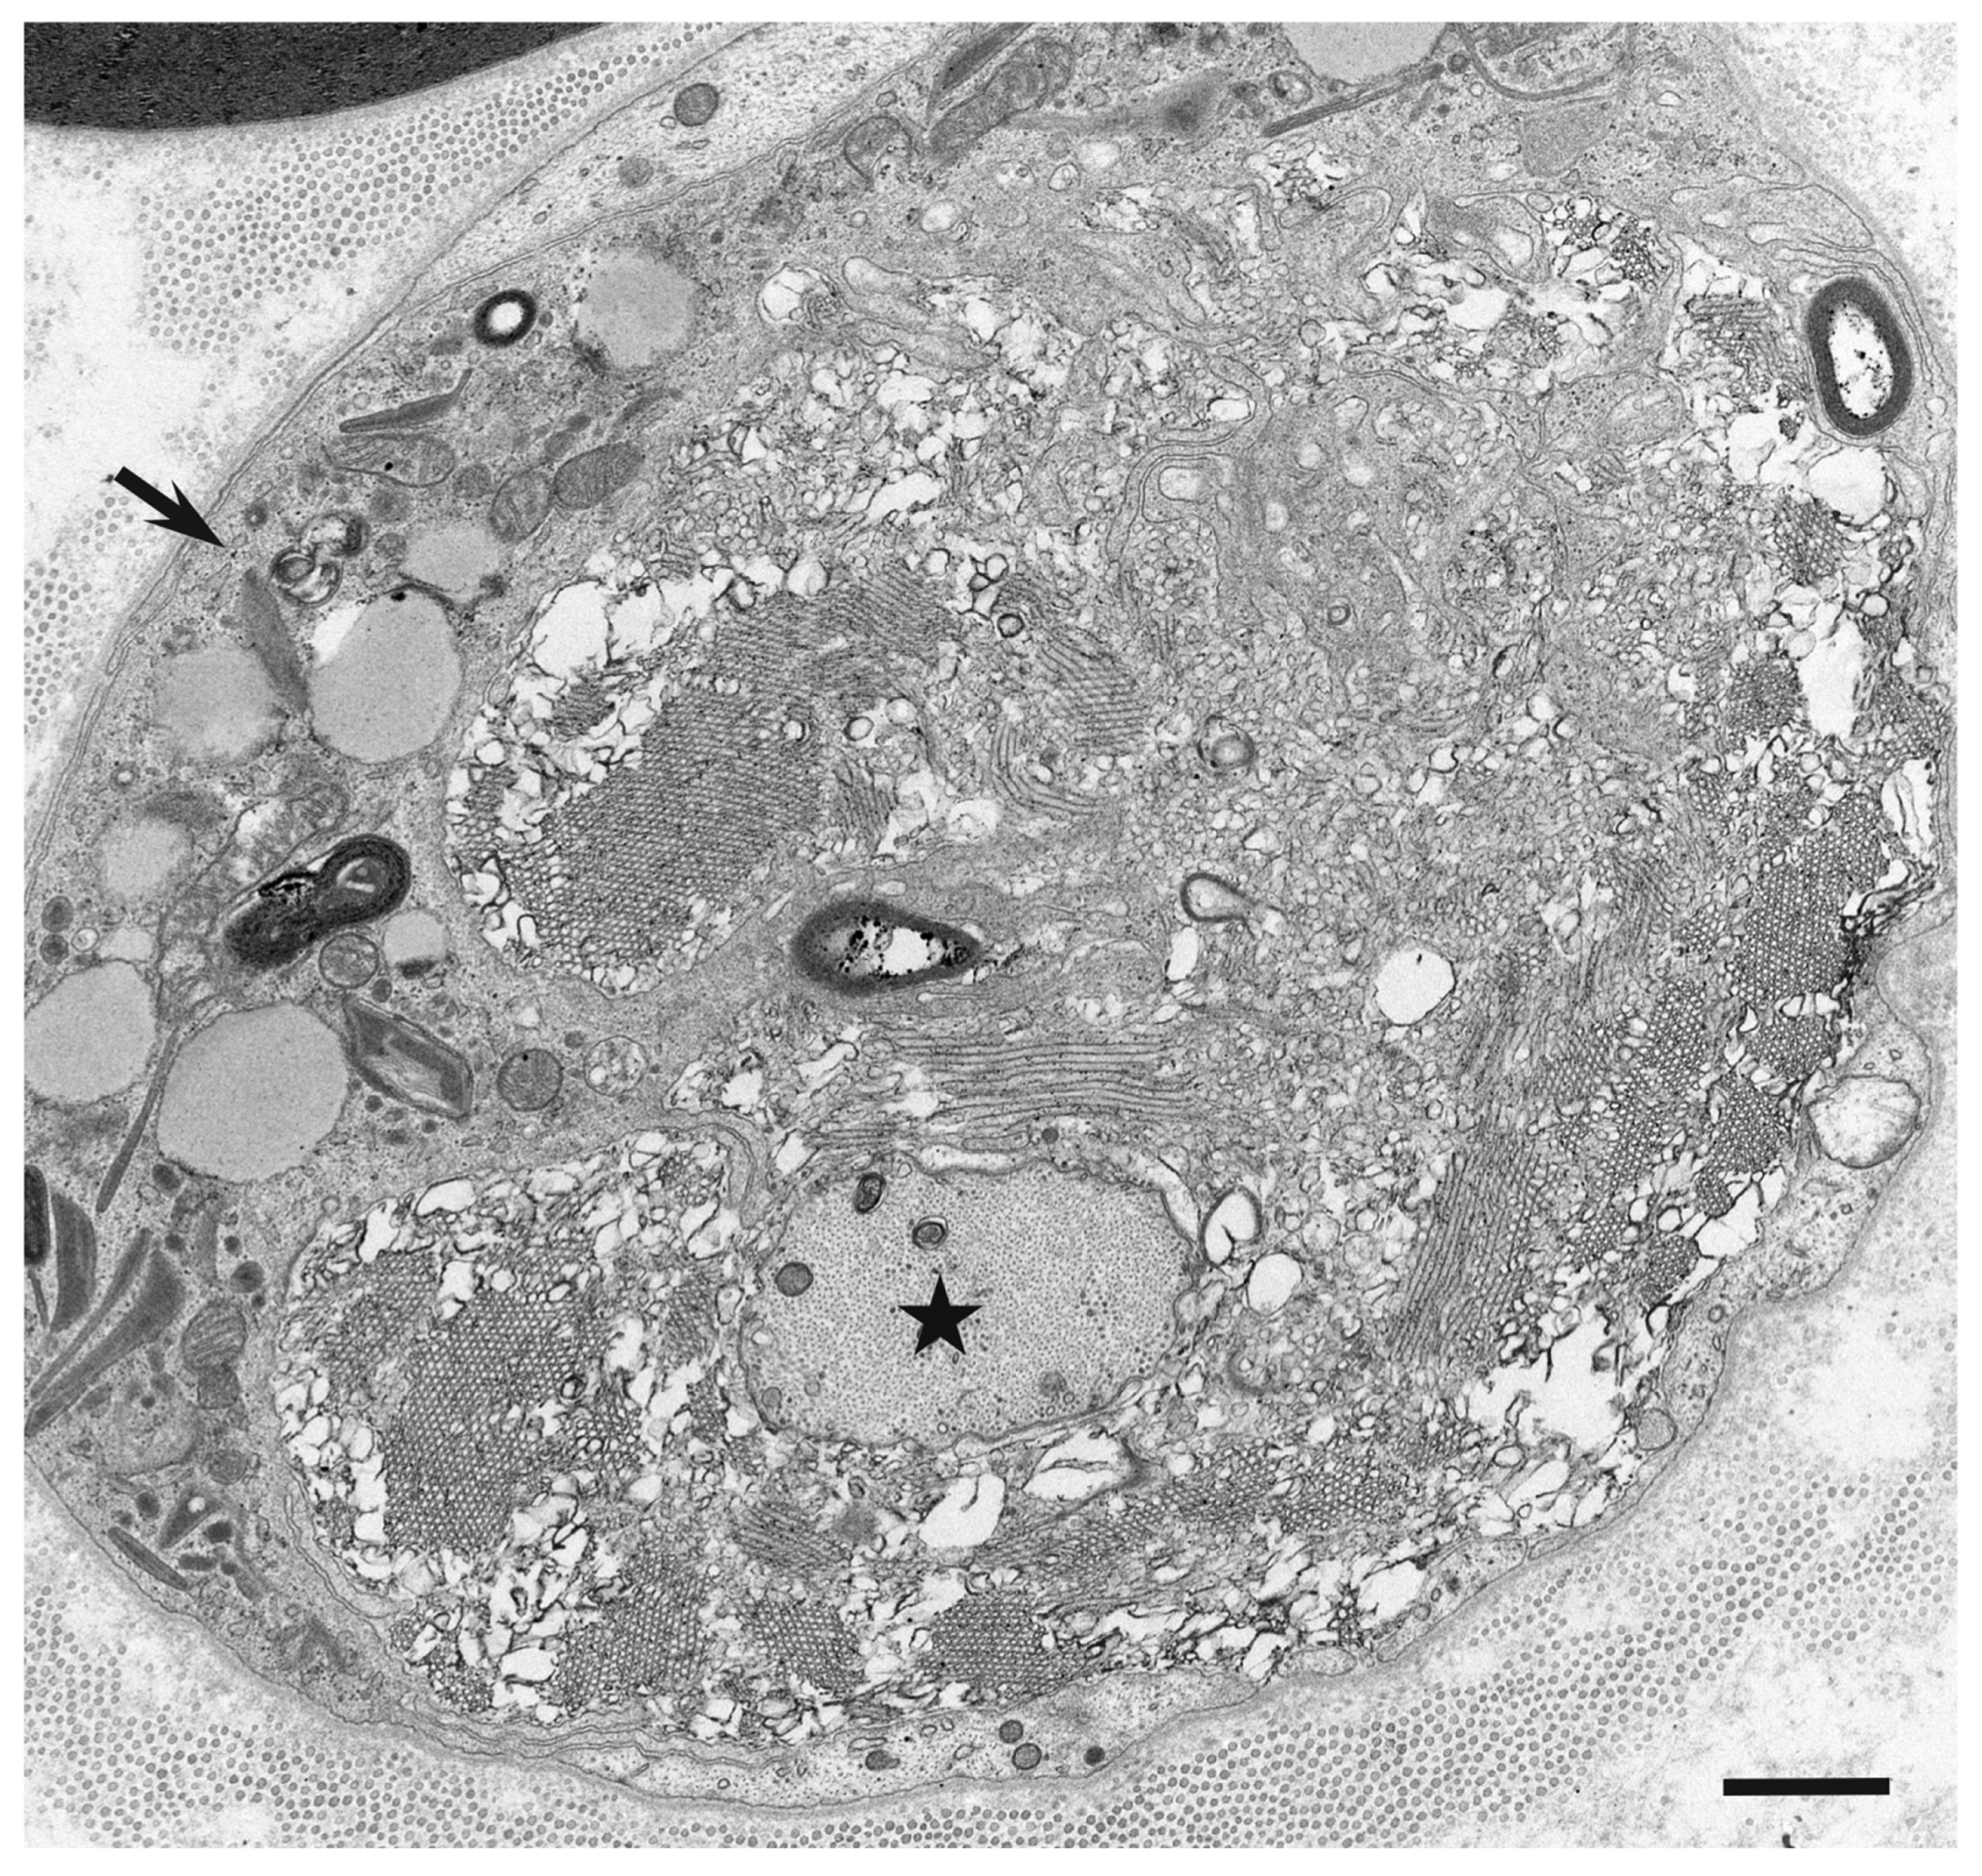

3. Morphology of Macrophages in Demyelination